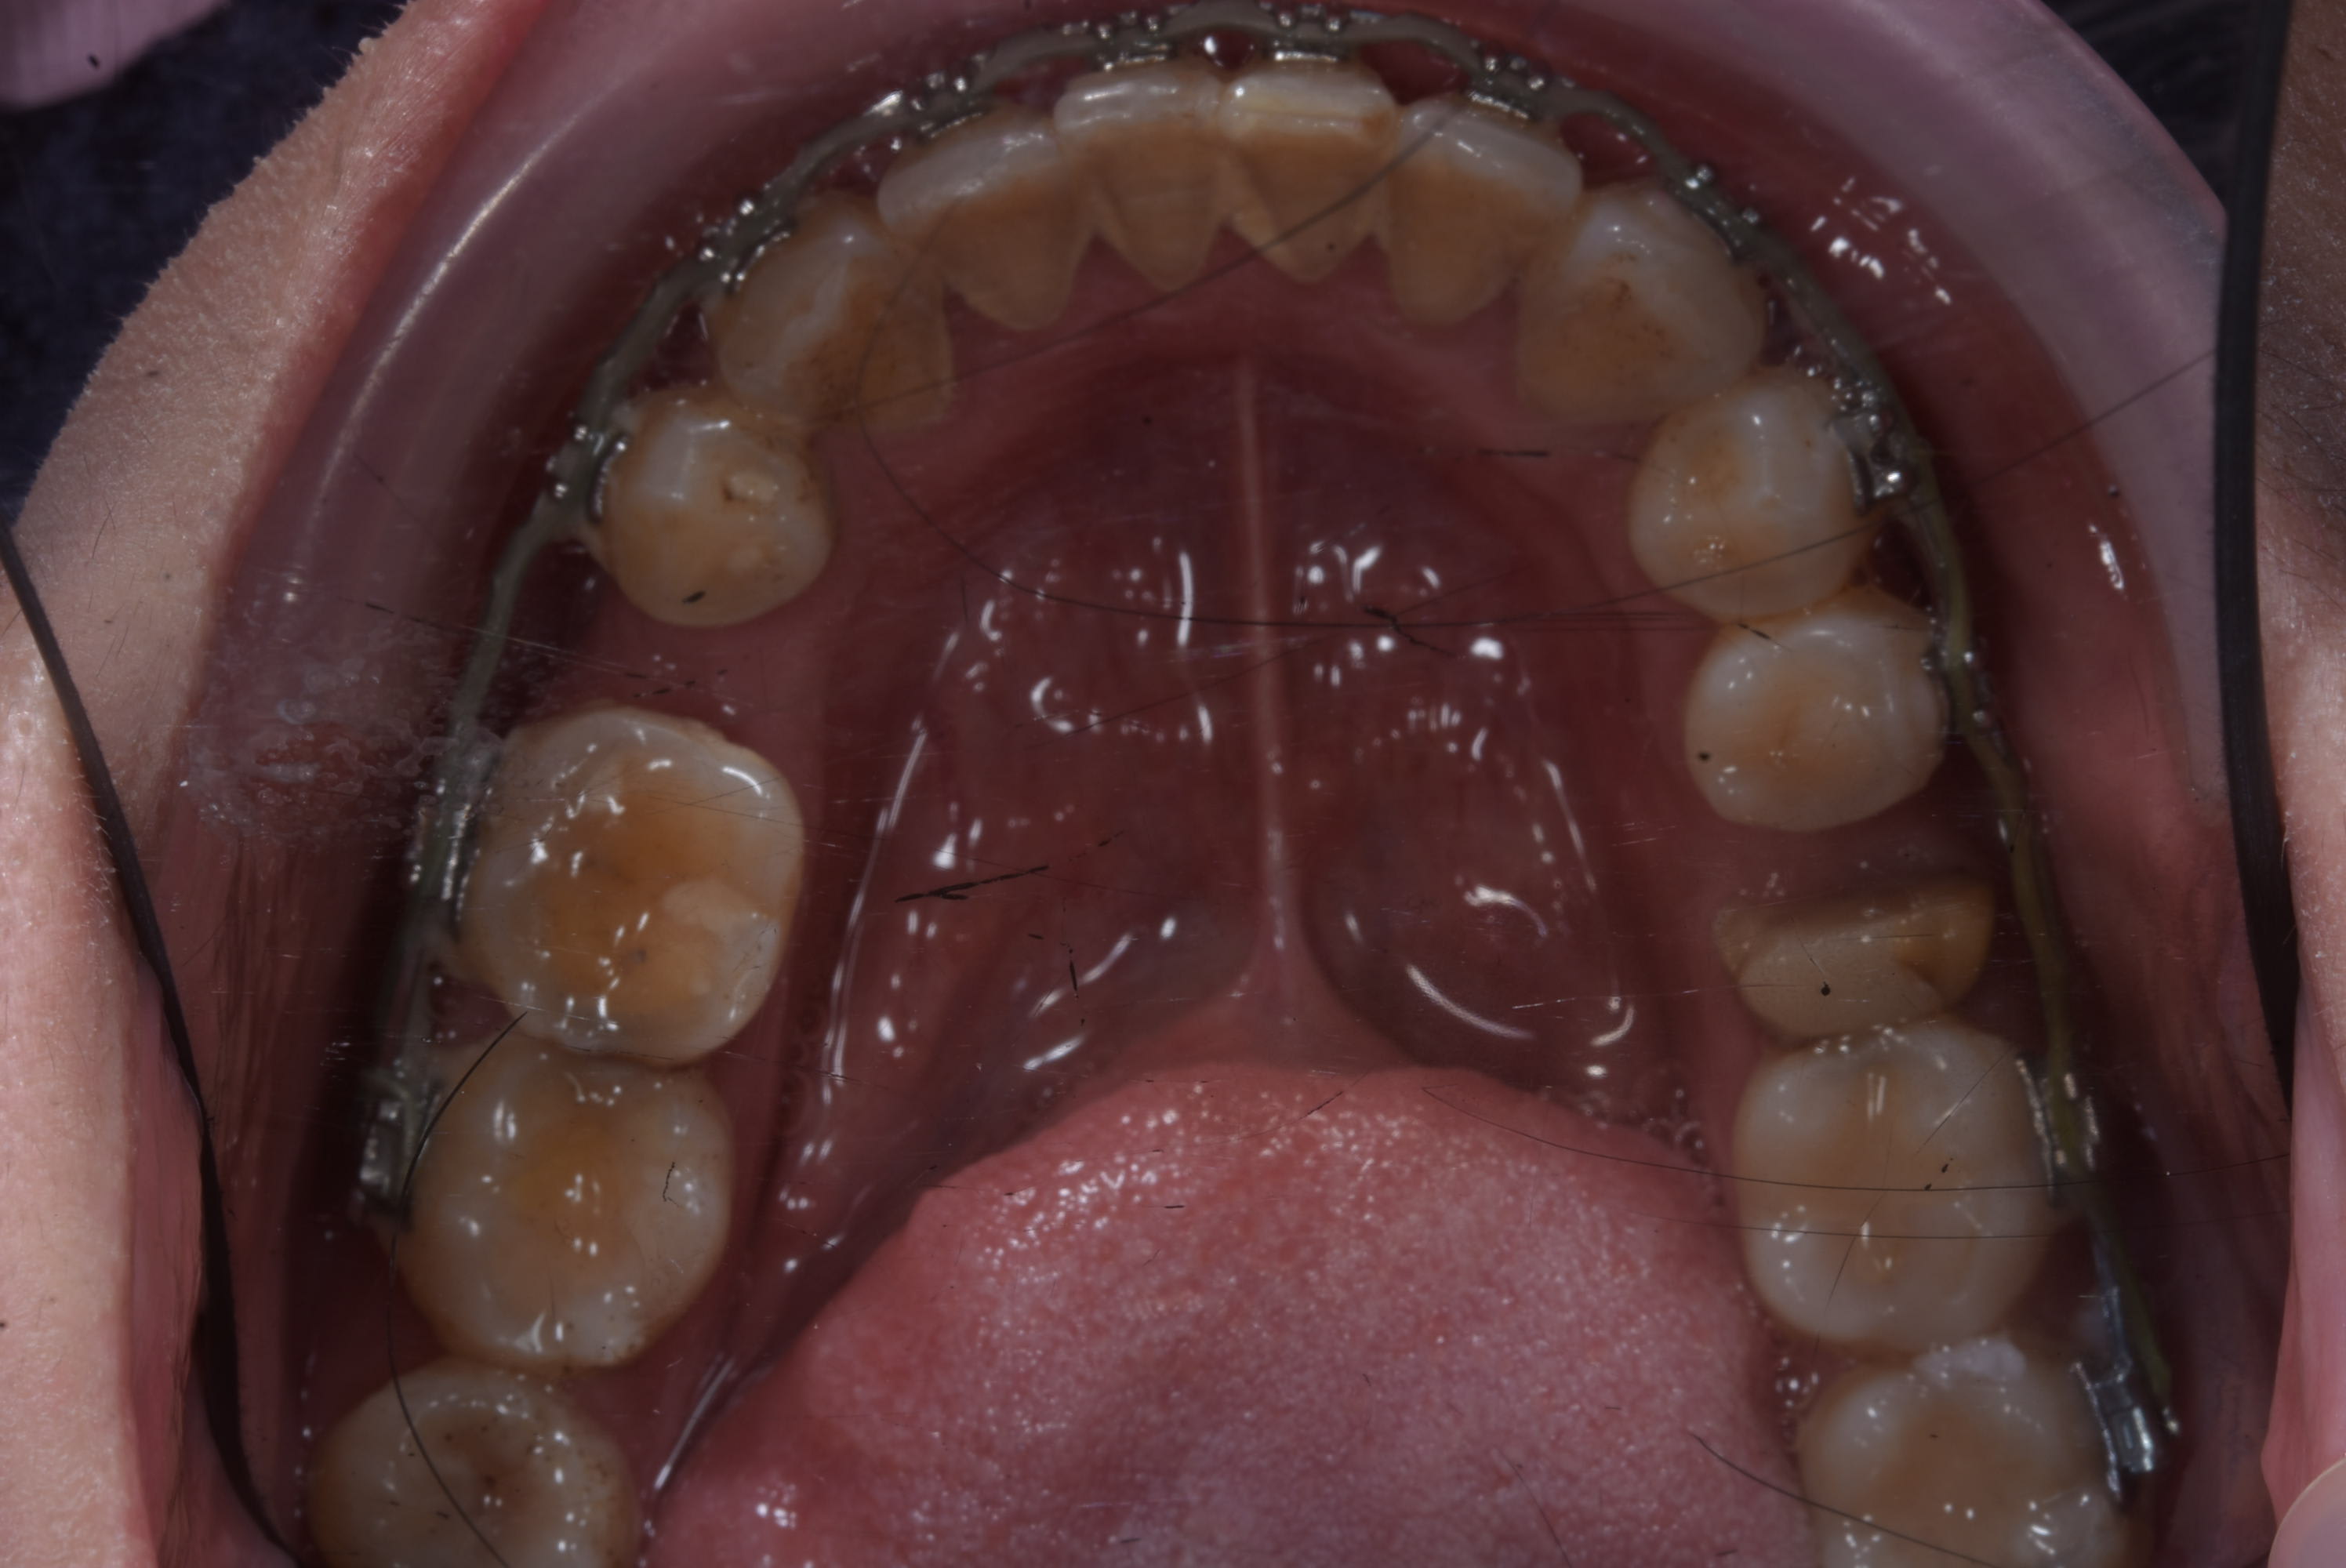

Rudy 12 ans et 3 mois.

Comme d'habitude motif de consultation douleur.

Un simple soin qui s'est transforme par la grâce à la magie de la gratuité CMU en endos couronne et qui dans 20 ans sera à refaire.

Pour commencer ce type de situation c'est ultra fréquent dans ma pratique privée, avec les expats aussi bien que les Cambodgiens. Enfant de famille " modeste " , friqué ou même de dentiste, donc ça ne me choque pas tant que ça.

Au niveau du traitement c'est simple et ça ne rallonge le traitement de 6 mois grand max sans avoir besoin d'acte supplémentaire ( comme des minivisses ).